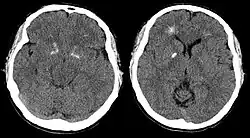

- Seizures (with or without hypocalcemia)

Adults with DiGeorge syndrome are a specifically high-risk group for developing schizophrenia. About 30% have at least one episode of psychosis and about a quarter develop schizophrenia by adulthood.[22]